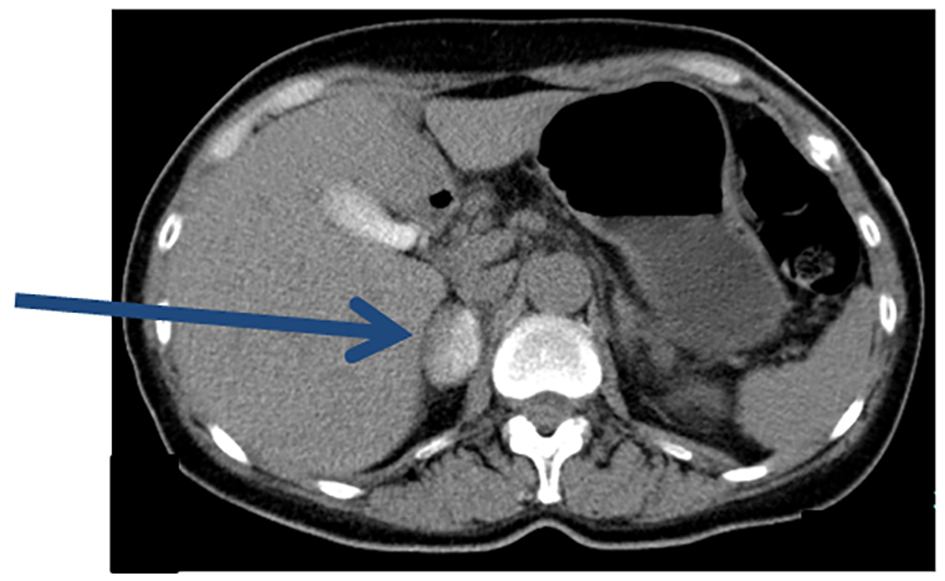

CT performed immediately after AVS revealed a hematoma and pooling of contrast medium in the right adrenal gland (Fig. 3). Although chest and back pain continued, the ECG and laboratory findings ruled out myocardial ischemia. Buprenorphine was administered for the pain and the patient was kept in hospital for bed rest. Her symptoms improved after 3 days and she was discharged.

![]() Click for large image | Figure 3. Plain CT after AVS. Immediately after AVS, pooling of contrast medium in the entire right adrenal gland was observed (arrow). |